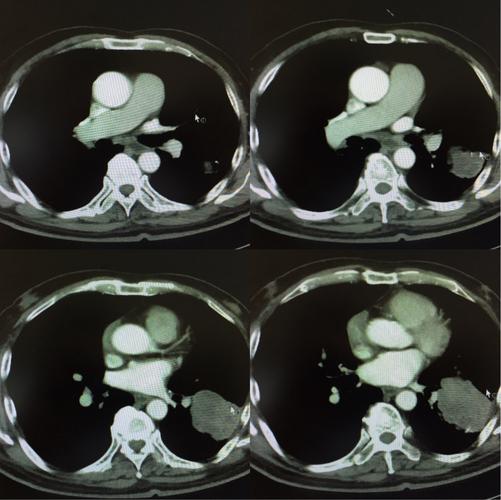

白银市第一人民医院肺癌mdt病历汇报(呼吸二科)

左肺下叶巨大软组织肿块 肺癌?

第三章 病例分析——肺癌

肺癌ct图片